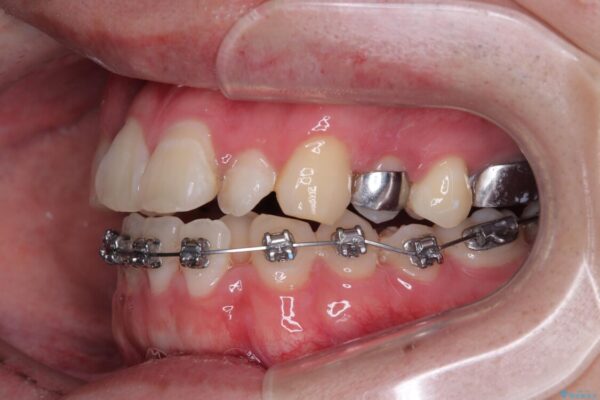

治療途中

• 1年でここまで変わる!歯列のがたつきと正中のズレを改善した矯正治療(メタルブラケット×MARPE) 治療途中画像

初診時の状態

・上下ともに歯がきれいに並びきらず、がたつきが見られました。

・上下の前歯の中心(正中)がずれています。

・特に上顎の幅が狭いため、下顎の歯列も内側に入り込み、歯が並ぶスペースが不足していました。

このような歯列の狭さに起因するデコボコを改善するために、**MARPE(骨に固定する上顎急速拡大装置)**を使用して、上顎の横幅を拡大し、これにより歯が並ぶためのスペースを確保し、メタルブラケットを用いて歯列を整えていく計画としました。